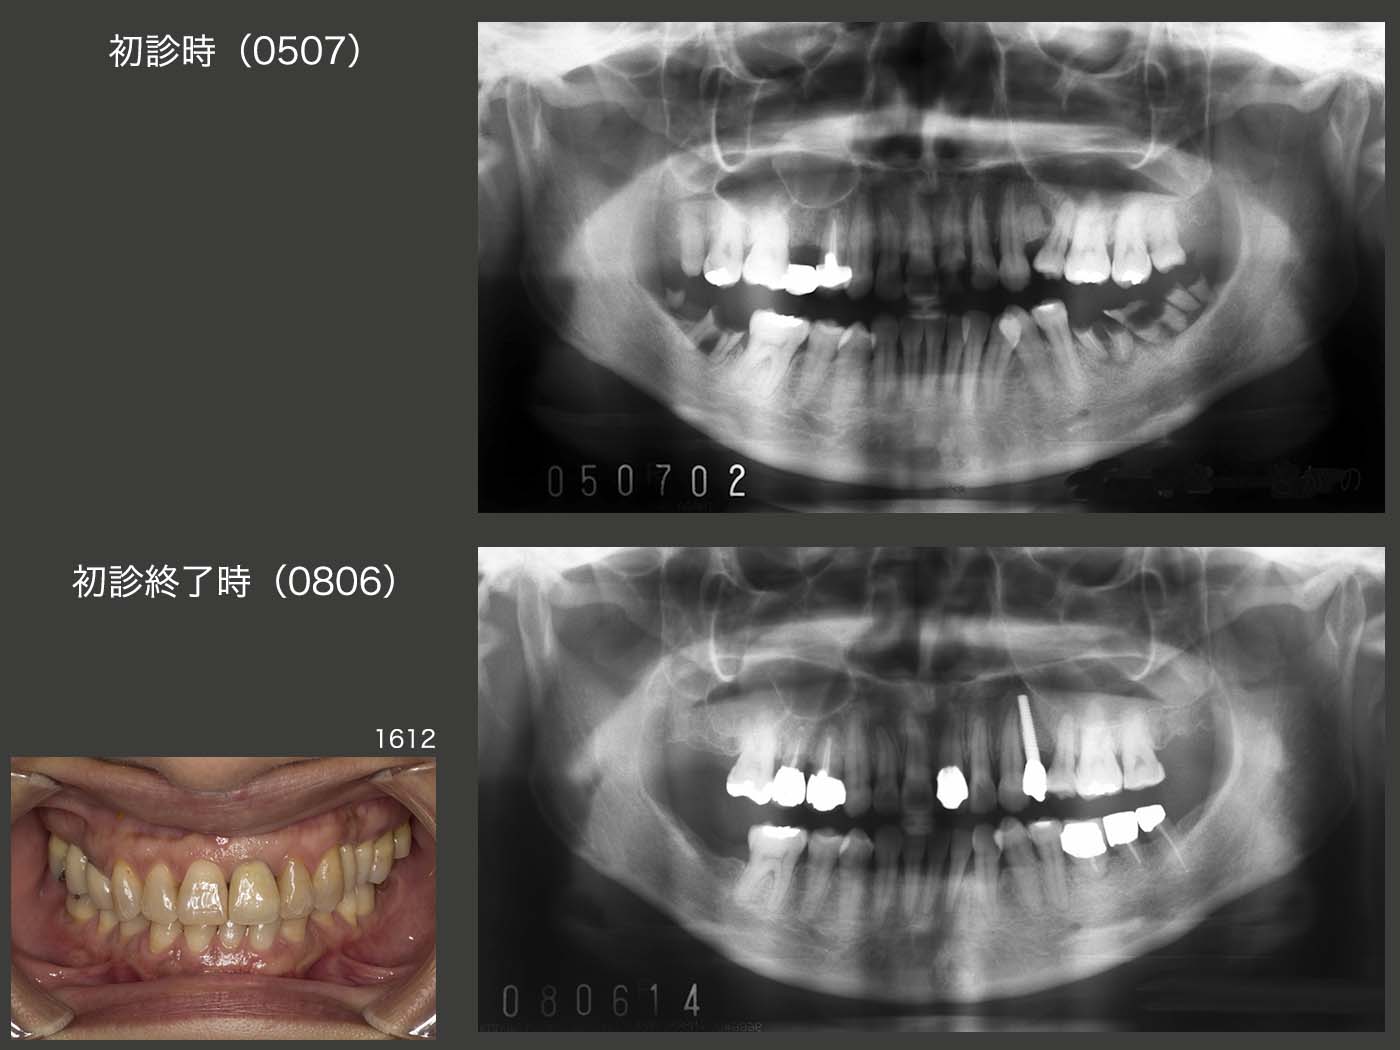

主訴の左上1を仮に修復し,一通りの基本治療を行った後の2006年2月,右上8の矮小歯を右上5部に移植した.さらに4月に,対合歯のない右上7を頰舌側に分割し,それぞれを左下に移植するという比較的難易度が高い移植を行った.続いて5月に,歯科矯正するに伴って必要がなくなる,舌側転位している左下2を左下の一番奥に移植した.これで左下は3本移植されたことになる.

左下の移植歯も固定源に利用し,06年11月に,下顎の歯科矯正に取りかかった.なお上顎は,少し前の8月から歯科矯正を開始している.08年3月,左上4部に,直径3mmの細いインプラントを植立した.ここは暫く人工歯を接着していたが,時々外れるので仕方なくインプラントを用いた経緯がある.両側がバージントゥースであり,しかも審美領域であることから今でも,補綴設計に悩む所である.